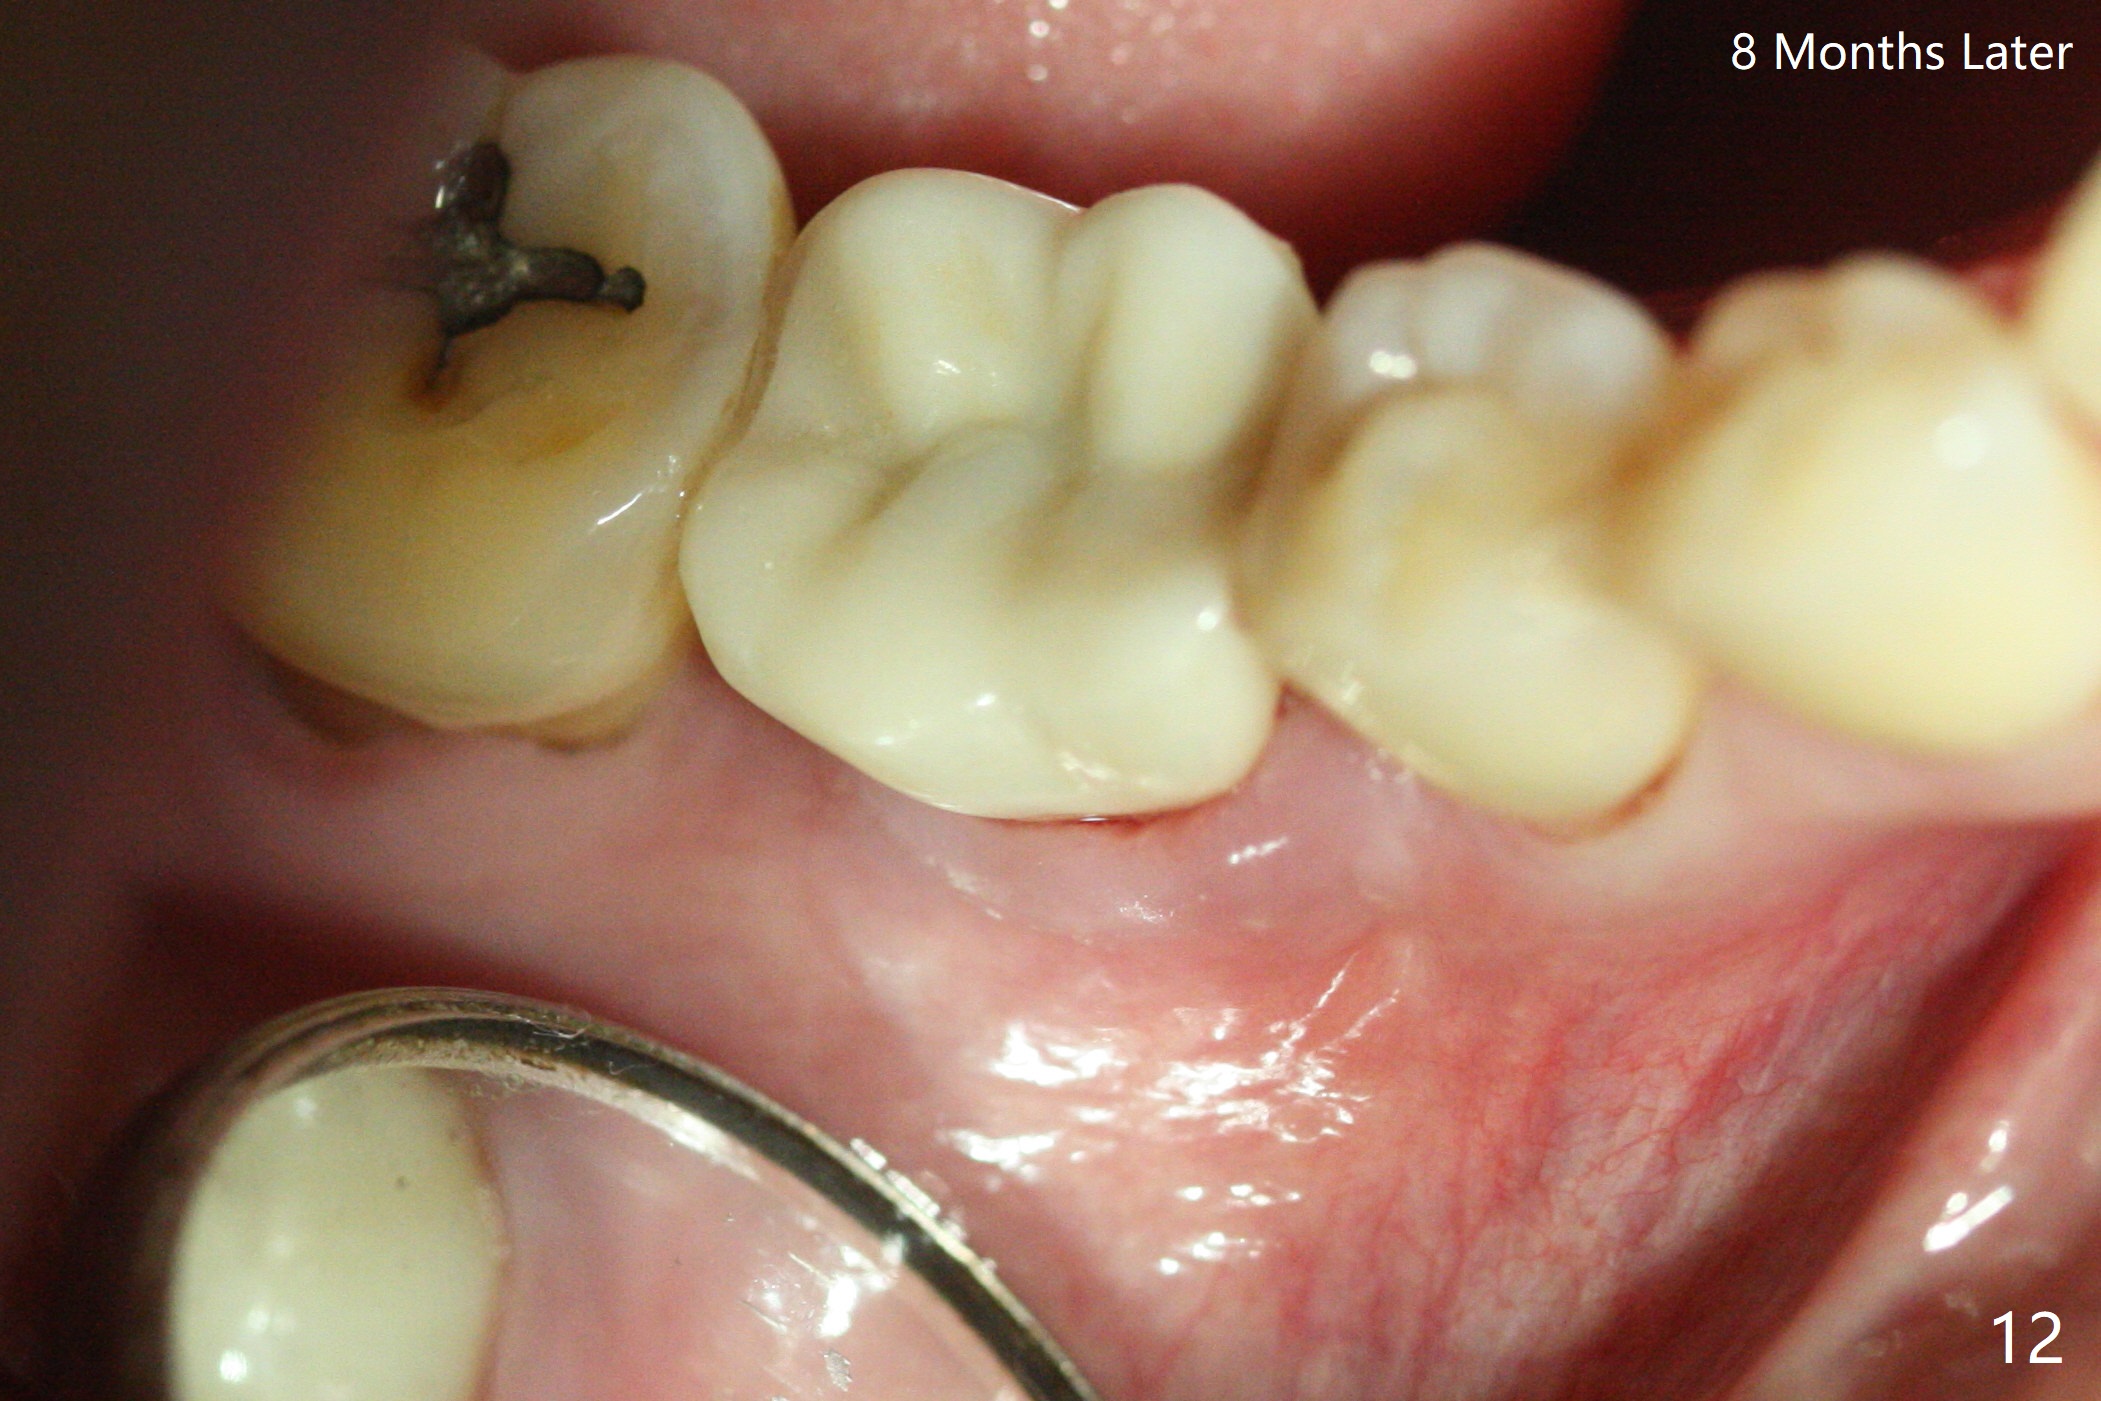

There is no symptom or sign of periimplantitis 3 years 8 months post 2nd bone graft (Fig.7-10). However, the patient complains of gingival hemorrhage 8 months later (Fig.11,12 (buccal), 13 (lingual view)). Water Pik is recommended.